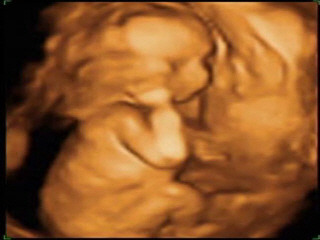

STAR-3D-01.jpg

첫째 아이 초음파 사진